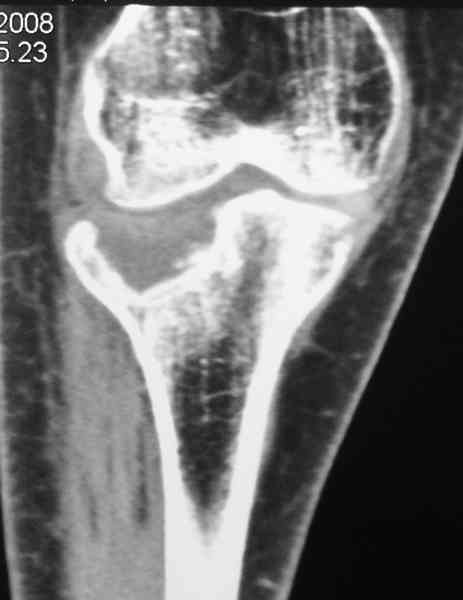

Re: Застарелый перелом 41С3

Уважаемый Абдурашид. Если нет противопоказаний , то из оперативных способов, я бы рекомендовал следующие: Полное замещение наружного мыщелка аллотрансплантатом либо открытая репозиция с элевацией и замещение дефекта ауто или аллокостью. В Ваших условиях , я бы рекомендовал второй способ. Во-время элевации необходимо разъединить фрагменты со стороны сустава ( надсечь скальпелем по линиям перелома, а затем тонким остеотомом их разъединить. При помощи долота произвести неполную остеотомию ( захватите не менее 1,5 - 2 см губчатой кости и поднять фрагменты, визуально отрепонировать и фиксировать 2-3 спицами. Дефект заместить костным ауто или аллатрансплантатом. Окончательная стабилизация пластиной ( лучше с угловой стабильностью, либо АВФ - позволит спокойно устранить угловую деформацию.

Недавно поступила больная через 1,5- 2 месяца.